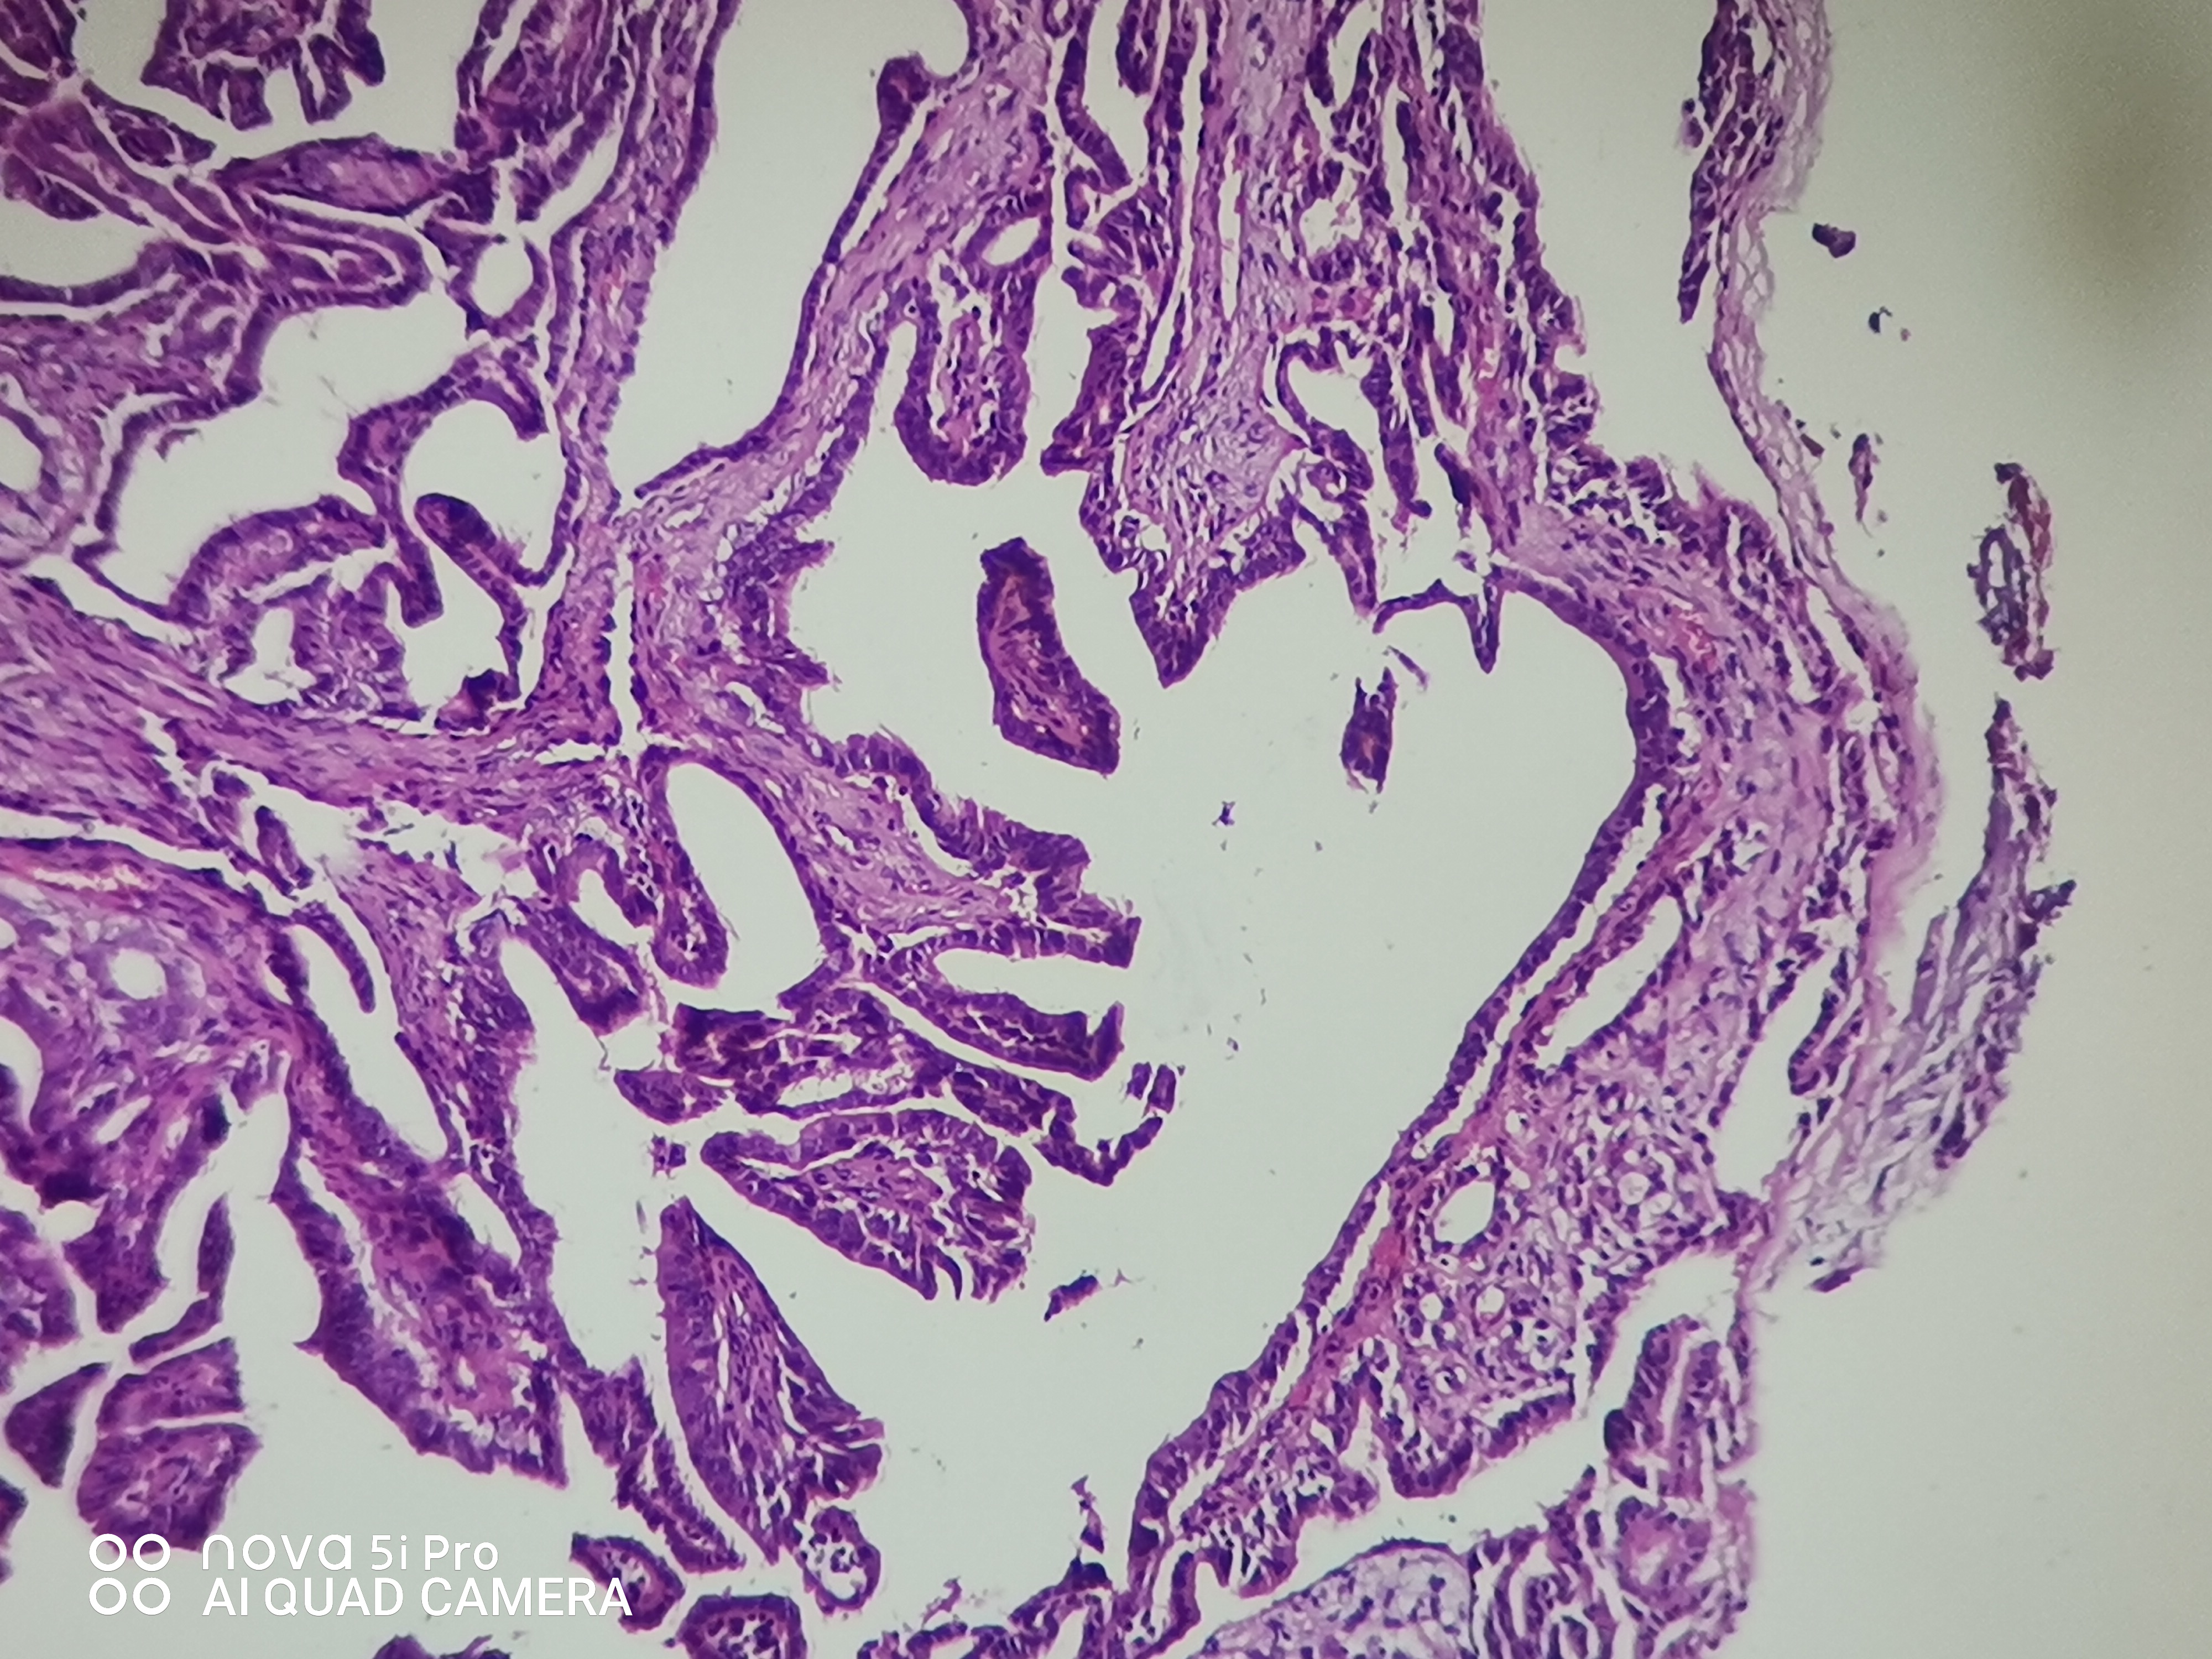

性别年龄41岁临床诊断混合痔,肛门肿块性质待查。

一般病史肛门肿块反复脱出5年,加重2月余。

标本名称肛门肿块

大体所见组织一块,大小约0.7*0.5*0.5cm,对半切开,实性灰白质中,全取。

高级别乳头状肿瘤

考虑:癌变!

乳头状汗腺瘤?

• 云子:  如果是肠上皮的话会有纤毛细胞,会有杯状细胞。杯状细胞的消失对应的是高级别肠上皮细胞病变,然而切片不支持高级别。女性外阴、肛门的这种乳头状生长模式十断头分泌现象,我更首先考虑乳头状汗腺瘤。个人意见,仅供参考!

图1可见断头式分泌,需要鉴别 汗腺肿瘤,标一下CK7.CK20.SATB-2.和P63。

这个病例的医生刚刚打电话联系我了,经省里专家远程会诊也是考虑乳头状汗腺瘤伴轻一中度非典。